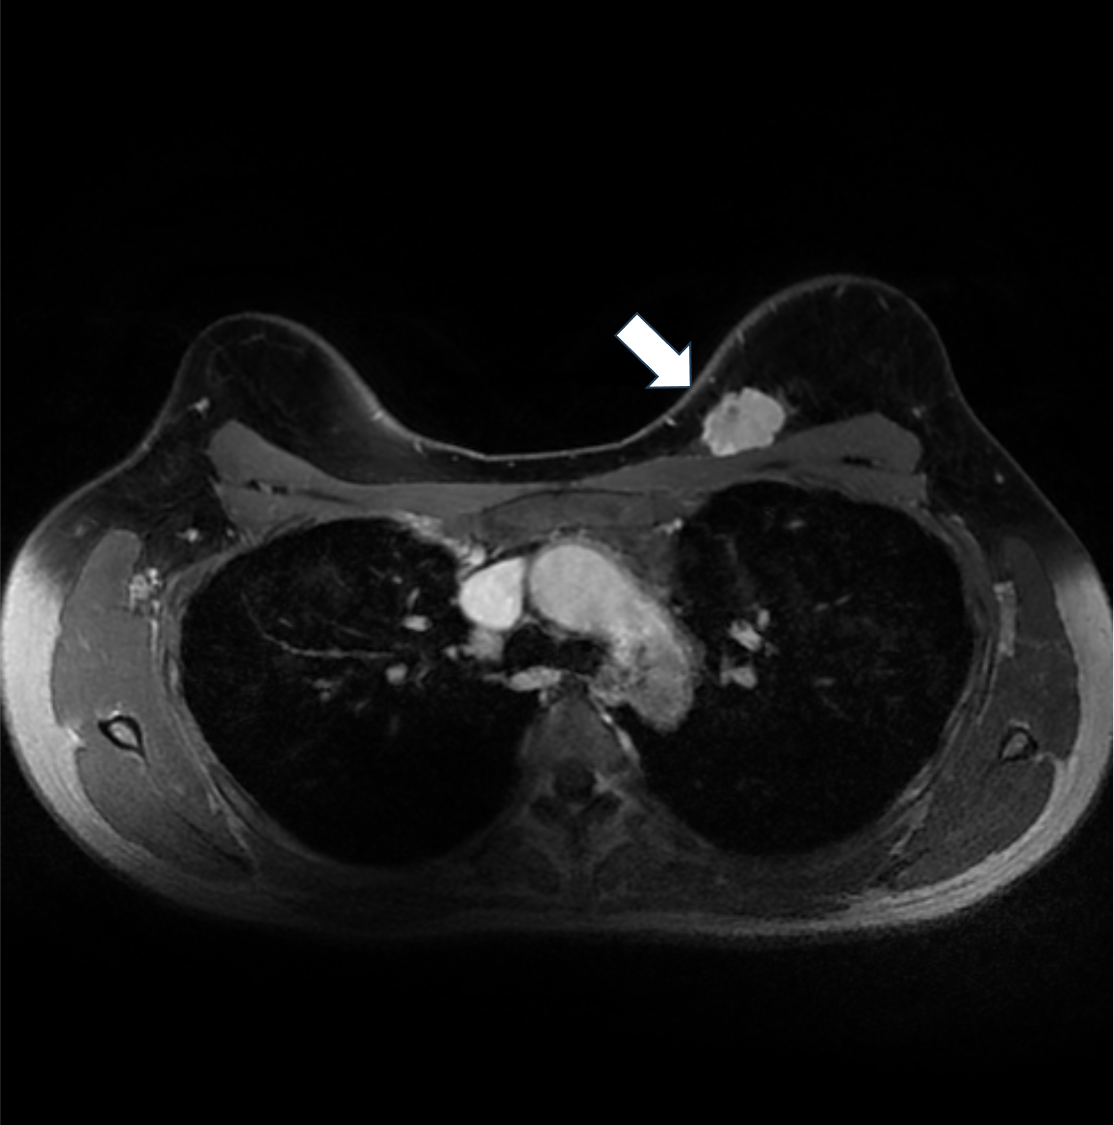

4. Ultrafast DCE (10phase目)

Ultrafast DCEでは早期から造影されている。血流豊富な腫瘍が示唆される。